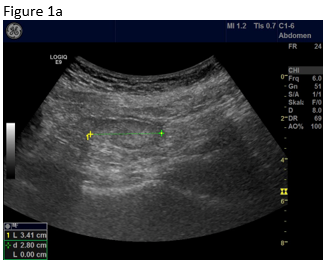

Figure 1: B-mode ultrasound using low frequency (a) and high frequency (b) revealed an isoechoic mass with a hypoechoic circumference. The mass was not adher-ent to the colon. Contrast enhanced ultrasound using low frequency (c) and high frequency (d) revealed that it was a non-enhancing segment of the omentum. Strain elastography showed that the lesion was stiffer than its sur-rounding tissue.